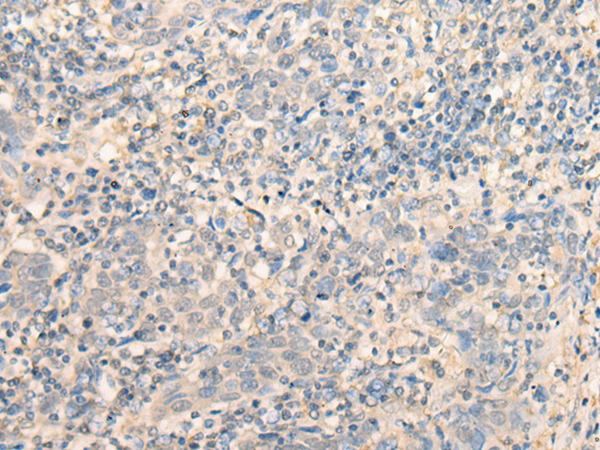

分类: 科研抗体货号: P09647别名: CGI-25应用: IHC反应种属: Human, Mouse